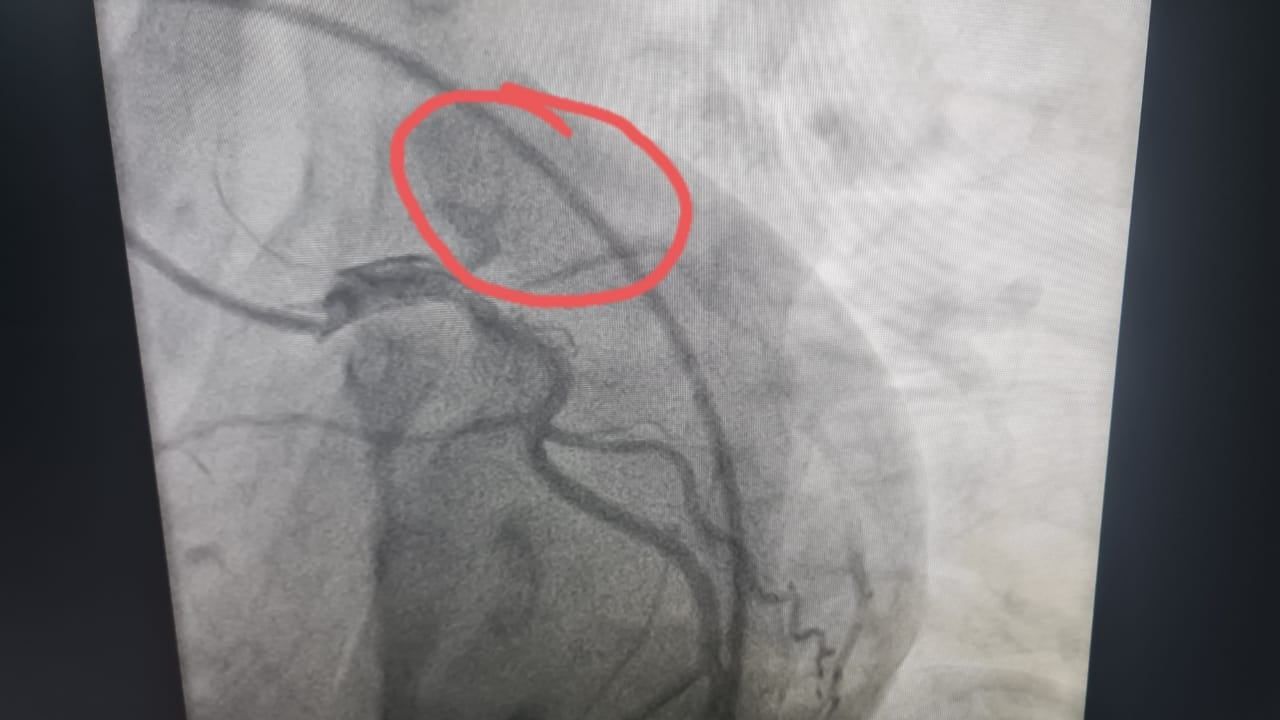

في واقعة طبية نادرة، نجح فريق طبى مساء أمس الأربعاء بوحدة قسطرة القلب بمستشفى طهطا العام  فى إنقاذ حياة شاب يبلغ من العمر 18 عامًا، بعد إصابته بجلطة حادة بالشريان الأمامي الرئيسي للقلب.

وأوضح الدكتور عمرو دويدار، وكيل بسوهاج، أن الشاب حضر إلى المستشفى فى حالة حرجة ومتأخرة نسبياً، وبعد إجراء رسم القلب والفحوصات اللازمة تبين وجود جلطة حادة بالشريان الأمامي — وهي من الحالات النادرة جدًا في هذا العمر علي المستوي العالمي.

وأضاف "دويدار" أنه فور الانتهاء من فحص المريض تم العرض علي الفريق الطبي بوحدة قسطرة القلب ، الذى قرر علي الفور إجراء قسطرة قلبية عاجلة لاستكشاف الشرايين التاجية للقلب حيث تبين أن الشريان الأمامي الرئيسي كان مسدودًا بالكامل، وتم فتح الشريان وتركيب دعامة بنجاح تام، واستقرت حالة المريض بعد العملية و يستكمل علاجه بالمستشفى.